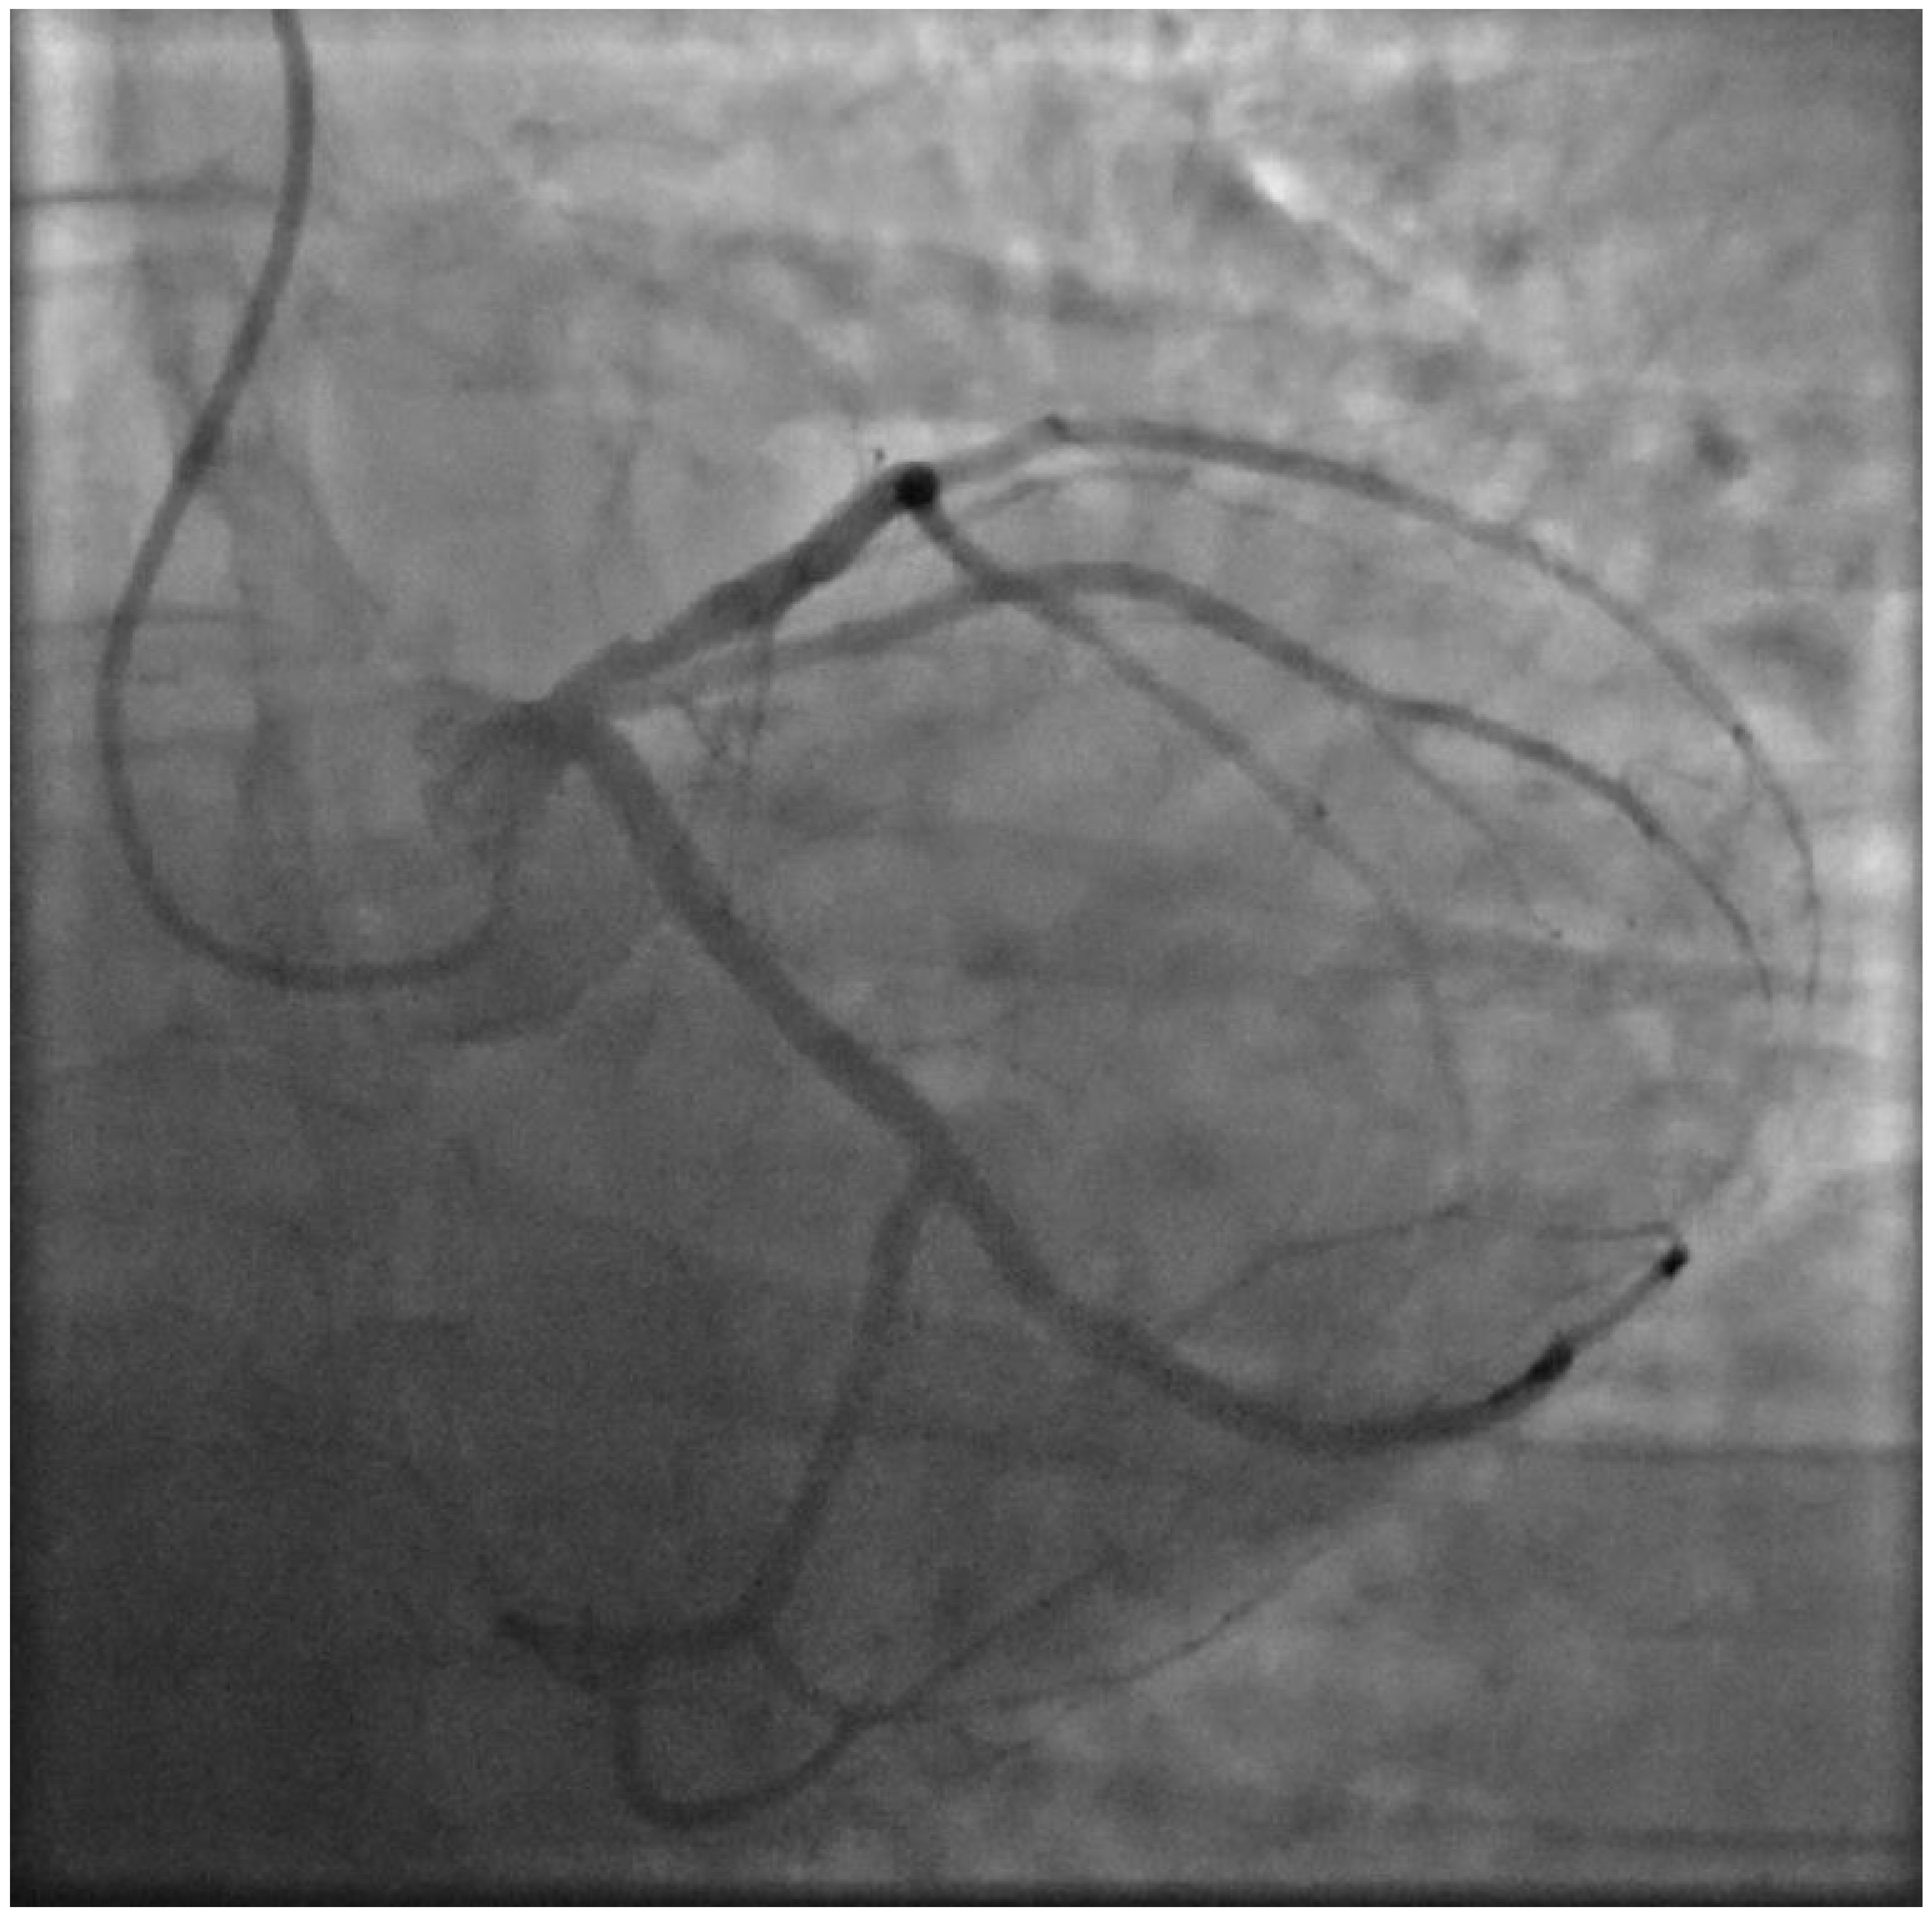

2. Case Presentation